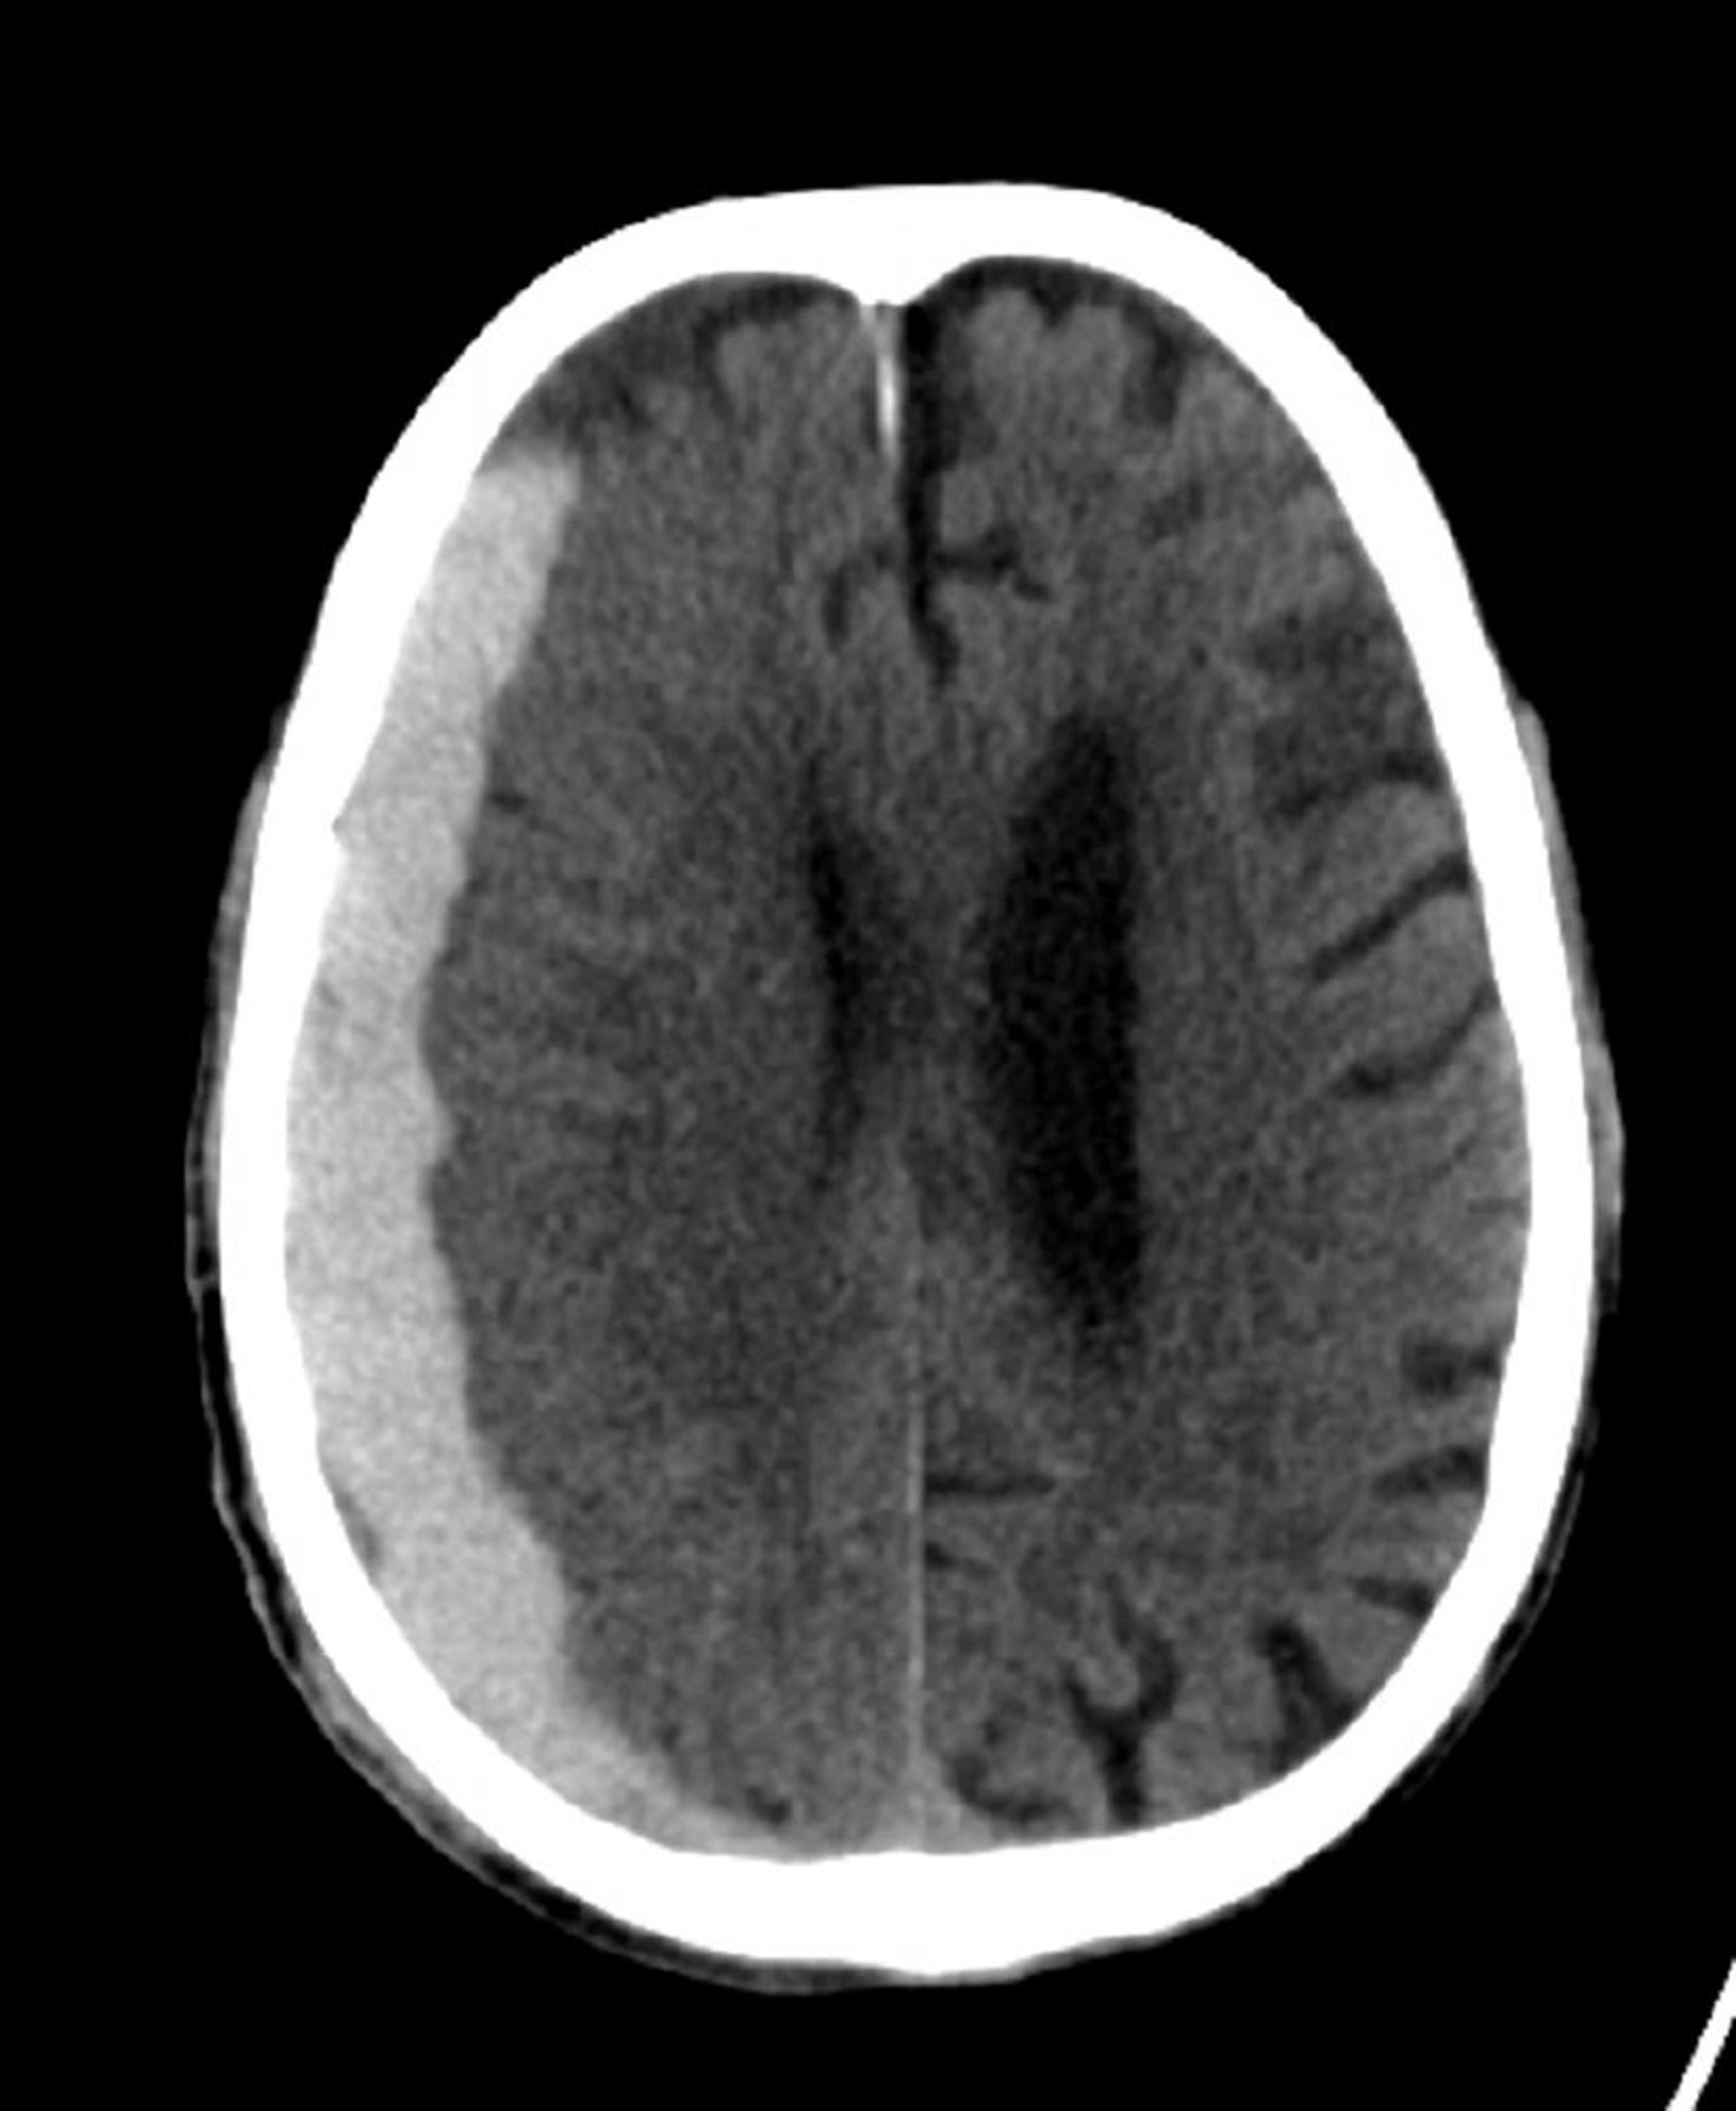

Субдуральное кровоизлияние (КТ)

Классические серповидные сгустки, распространяющиеся по линиям шва.